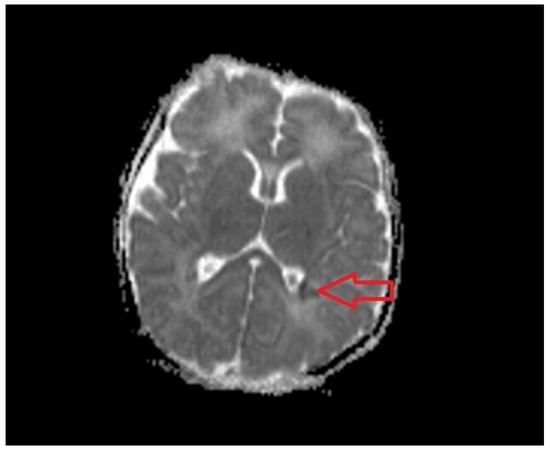

- Wisnowski, J.L.; Wintermark, P.; Bonifacio, S.L.; Smyser, C.D.; Barkovich, A.J.; Edwards, A.D.; de Vries, L.S.; Inder, T.E.; Chau, V.; Guidelines, N.B. Publications Committee Neuroimaging in term newborns with neonatal encephalopathy. Semnin. Fetal Neonatal. Med. 2021, 26, 101304. [Google Scholar] [CrossRef]

- Li, A.M.; Chau, V.; Poskitt, K.J.; A Sargent, M.; A Lupton, B.; Hill, A.; Roland, E.; Miller, S.P. White Matter Injury in Term Newborns with Neonatal Encephalopathy. Pediatr. Res. 2009, 65, 85–89. [Google Scholar] [CrossRef]

- Hayman M, VAN Wezel-Meijler G, van Straaten H: Punctate white-matter lesions in the full-term newborn: Underlying aetiology and outcome. Eur. J. Pediatr. Neurol. 2019, 23, 280–287. [CrossRef] [PubMed]